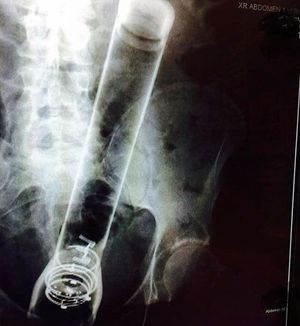

Finding a random mag-light in a patients’ rectum might be a little unpleasant, especially when you’re having your patient bend over and a beam of light shines straight in your face coming right from this persons cornhole! In medical terms, a foreign body or object is something that is in the body but does not belong there. Small foreign bodies are pretty common, found in the ears, nose, airways, and stomach. They can irritate, eventually causing inflammation and scarring of the tissue, not to speak about the infections they might bring.